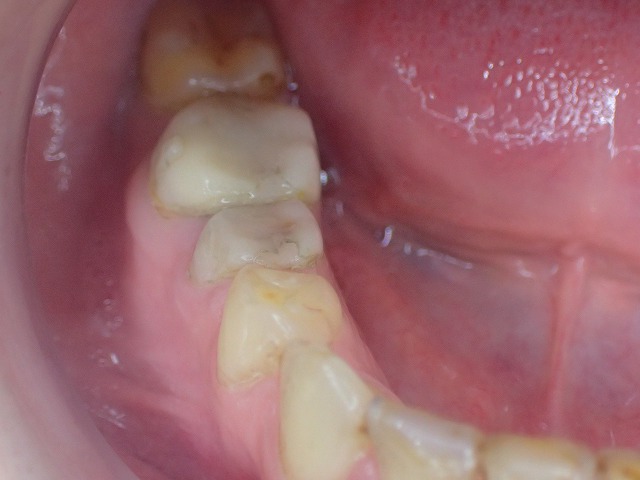

右下

同じくコンタクトしていません。

cad/cam冠はすぐに減るので

お口の中を大切に思いう人は、入れないほうが

良いと思います。